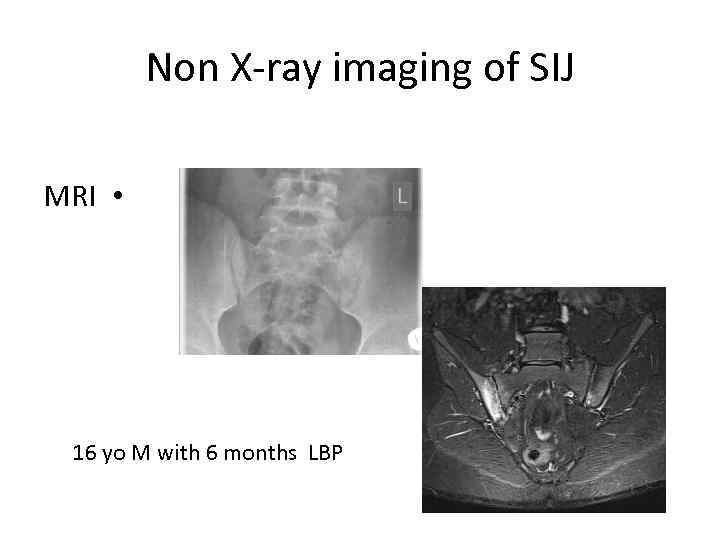

Non X-ray imaging of SIJ MRI • 16 yo M with 6 months LBP